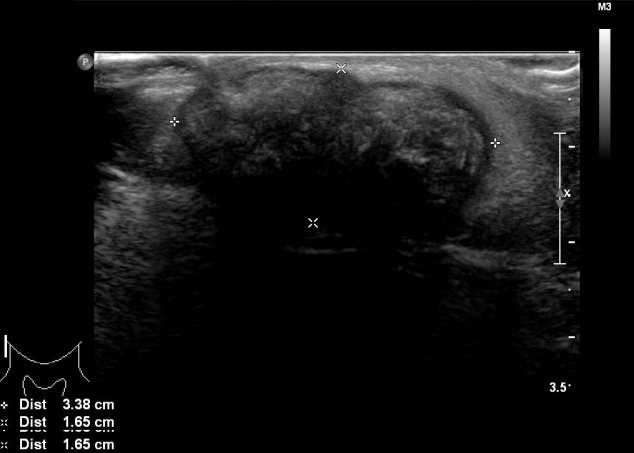

進行超聲檢查以確定腫塊是否為腮腺腫瘤,并顯示與腮腺分離的異質(zhì)腫塊(圖 2)。 進行了頸部對比增強計算機斷層掃描和超聲引導(dǎo)穿刺活檢。 在右下頜角,它表現(xiàn)為邊界清楚、分葉狀和不均勻強化的腫瘤,在皮下脂肪層和淺表肌肉腱膜系統(tǒng)中有鈣化部分(圖 3)。 穿孔活檢顯示與毛母質(zhì)瘤一致的特征,并且在超聲引導(dǎo)下對頸部淋巴結(jié)進行抽吸活檢時未發(fā)現(xiàn)腫瘤細(xì)胞。

圖 2:超聲檢查顯示與腮腺分離的異質(zhì)性病變